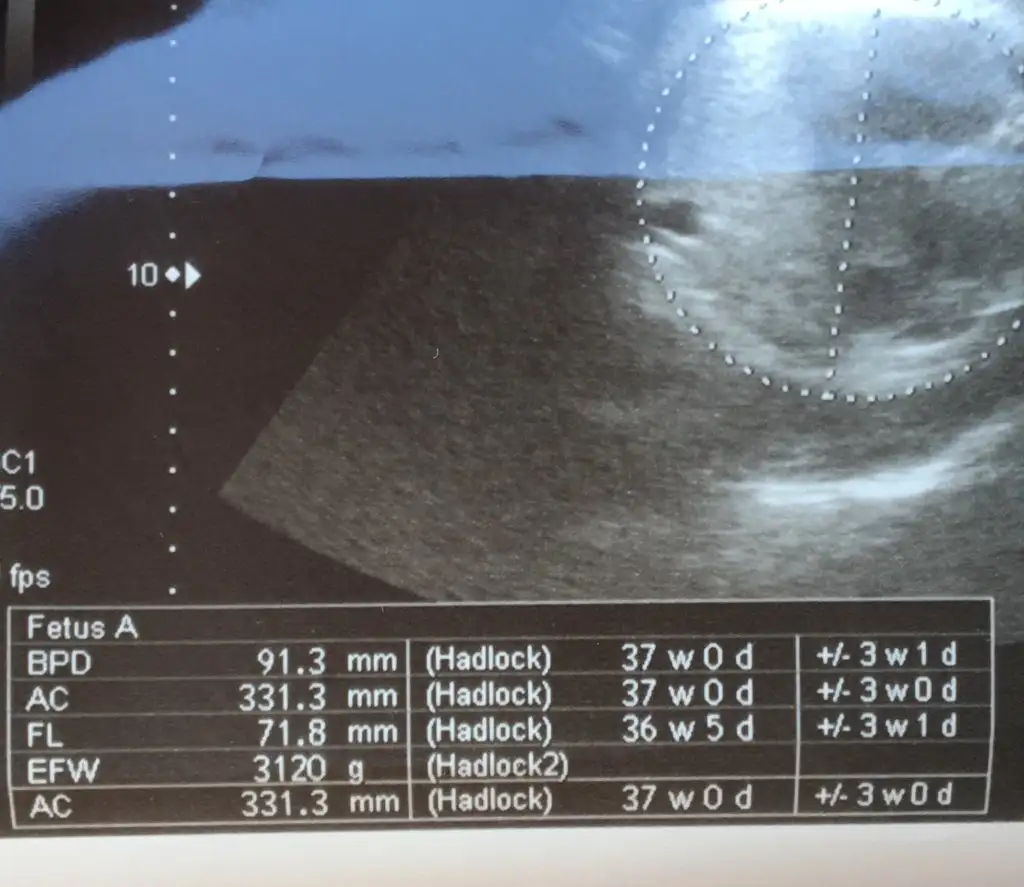

Canım benim de son iki kontrolün degerleri aynı boy ve kilo hiç ilerlememiş görünüyor. Doktora sordum son haftalarda ölçümler dogru olmuyor dediHerkese selamben sayfaya çok fazla bakamıyorum baksam bile yazılanları okuyorum cevap yazamıyorum kızlar... çok güzel doğum haberleri okudum , herkesim gözü aydın olsun darısı biz bekleyenlerin basına inşallah bugün 37+6 kontrolüm vardı ama kontrolde 37 çıktım, neyse 1 hafta oynar dedim sonra eve geldim 19 ekim de ki usg değerlerine baktım ve o günden bugüne doğru düzgün ilerleme olmadığını gördüm, sadece kilo almış bebeğim .. doktorum herşey normal bir sıkıntı yok dedi ama benim içime kurt düştü şimdi ... haftaya tekrar kontrole çağırdı ki ben artık doğum için tarih verir diyordum İlk kızım sezaryen çünkü ... gerçi bebeğim baş aşağı dönmüş ... şimdi sizden ricam eklediğim usg fotolarında haftalarına bakıp yorumlar mısınız? İlk yüklediğim 19 ekim , diğeri 4 kasım ...şimdiden hepinize teşekkür ederim